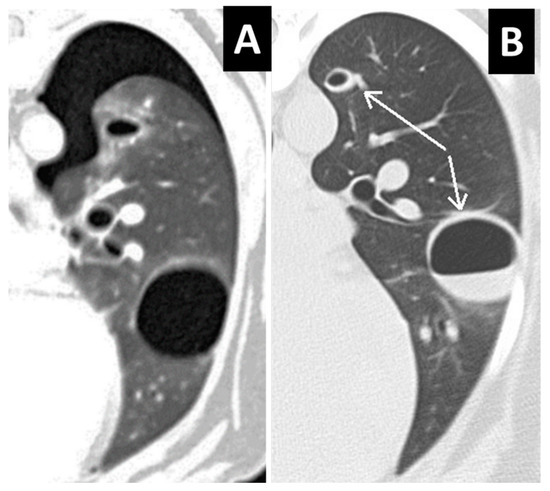

Figure 7.

Comparison of computed tomography (CT) images of the left lung in a traumatized dog with Type 2 and Type 4 lung lacerations. (A) The first CT examination showed two cystic, air-containing lesions and ipsilateral pneumothorax (without rib or vertebral fractures). (B) After 5 days, CT showed air–fluid levels in both lesions and a small amount of air visible in the pleural cavity.